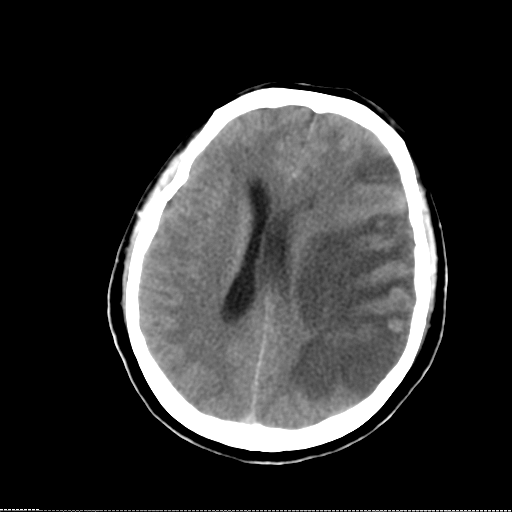

图1:头颅CT提示:左侧颞叶大面积脑梗塞,中线移位

入院第1天使用重庆海威康医疗仪器有限公司无创颅内压监测仪检查患者颅内压,提示双侧颅内压增高,分别为右侧462mmH2O、左侧372 mmH2O,4h后复查右侧567mmH2O、左侧549mmH2O,第2天复查右侧525mmH2O、左侧585mmH2O,因患者临床症状好转,而无创颅内压检测提示颅内压呈持续上升状态,故引起临床重视,第3日患者症状突然加重,复查头颅CT提示“左侧颞叶大面积脑梗死,中线移位”(见图1)。此时复查无创颅内压检测:分别为右侧525mmH2O、左侧717mmH2O,双侧压力差>150mmH2O,提示脑疝可能(见图2)。之后转脑外科行手术减压治疗。起病后无创颅内压检测提示颅内压逐渐增高,并有脑疝趋势(见图3),为疾病的及时诊断提供了帮助。